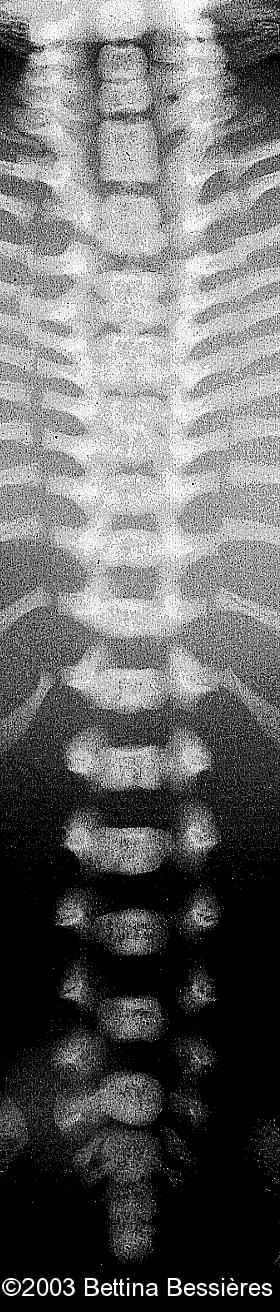

Abnormal vertebrae.

case0093-17

• fused vertebrae

• abnormal vertebrae.

The radiohumeral fusion, and abnormal vertebrae:

case0093-08

case0093-09